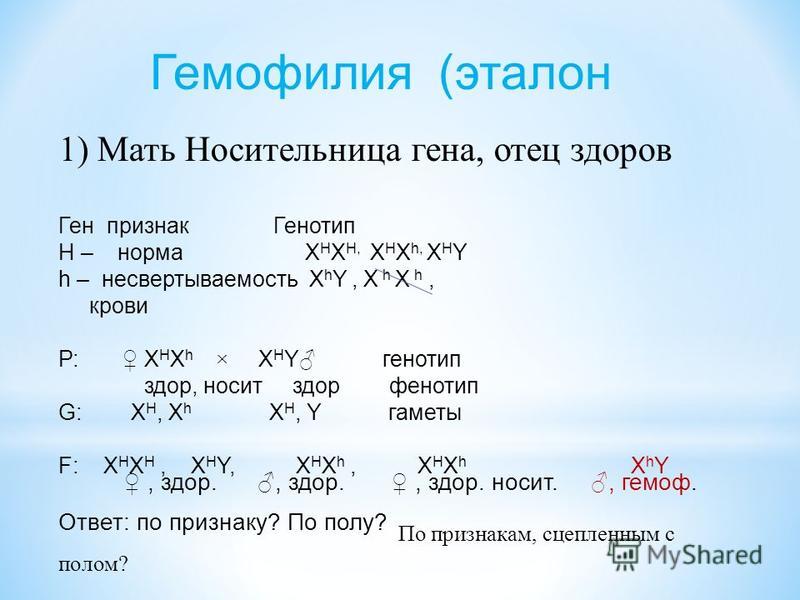

Генетика гемофилии: рецессивные гены и их проявления